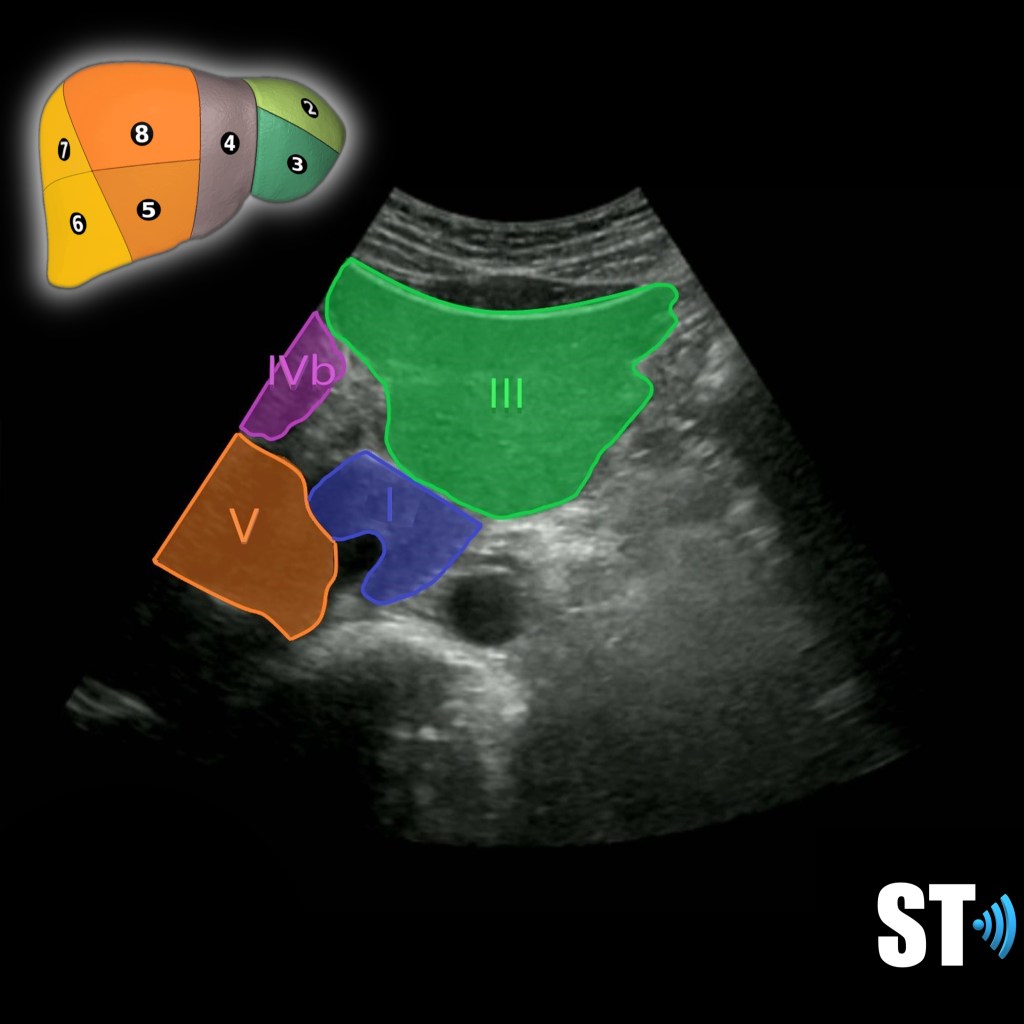

Segment IVb, V and VI

Segment IV is subdivided into IVa and IVb, superior and inferior and is located between the left and middle hepatic veins.

Segment V is inferior to the portal plane between the middle and right hepatic veins.

Segment I is the caudate lobe.